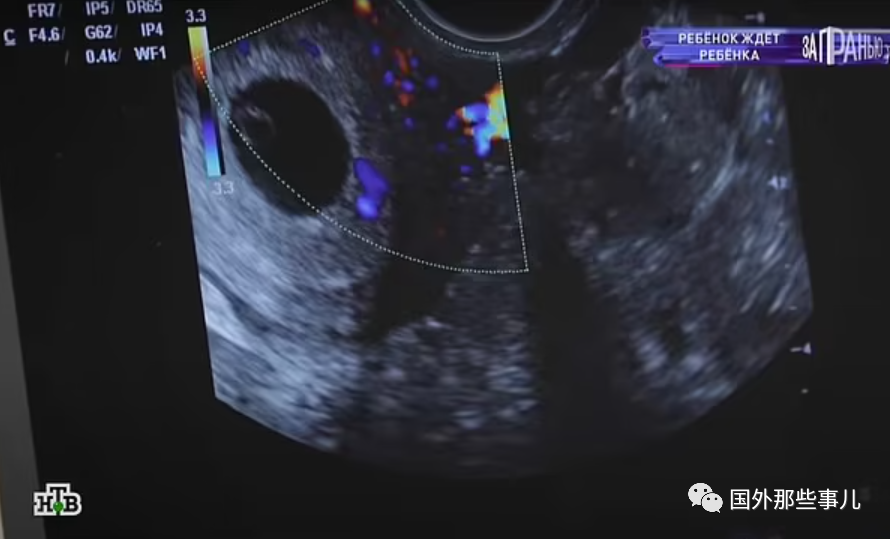

近日,俄罗斯一名12岁的女孩被检查出已经怀孕,据悉女孩最初告诉她的男友自己已经16岁了。女孩坚持要生下孩子,并表示将和42岁的母亲一起抚养。目前,当地警方已经开始调查此事。

据外媒9月17日报道,这名女孩叫达莎,来自俄罗斯。近日,她和母亲上了一档节目讲述了自己的遭遇。达莎表示,她最初告诉男友自己已经16岁了,实际上她才12岁。而他的男友年龄大于18岁。

如今,达莎和男友已经分手。但她表示很高兴怀孕并打算生下孩子,和她42岁的母亲埃琳娜一起抚养。达莎表示,会继续上学,将来希望成为一名牙医。